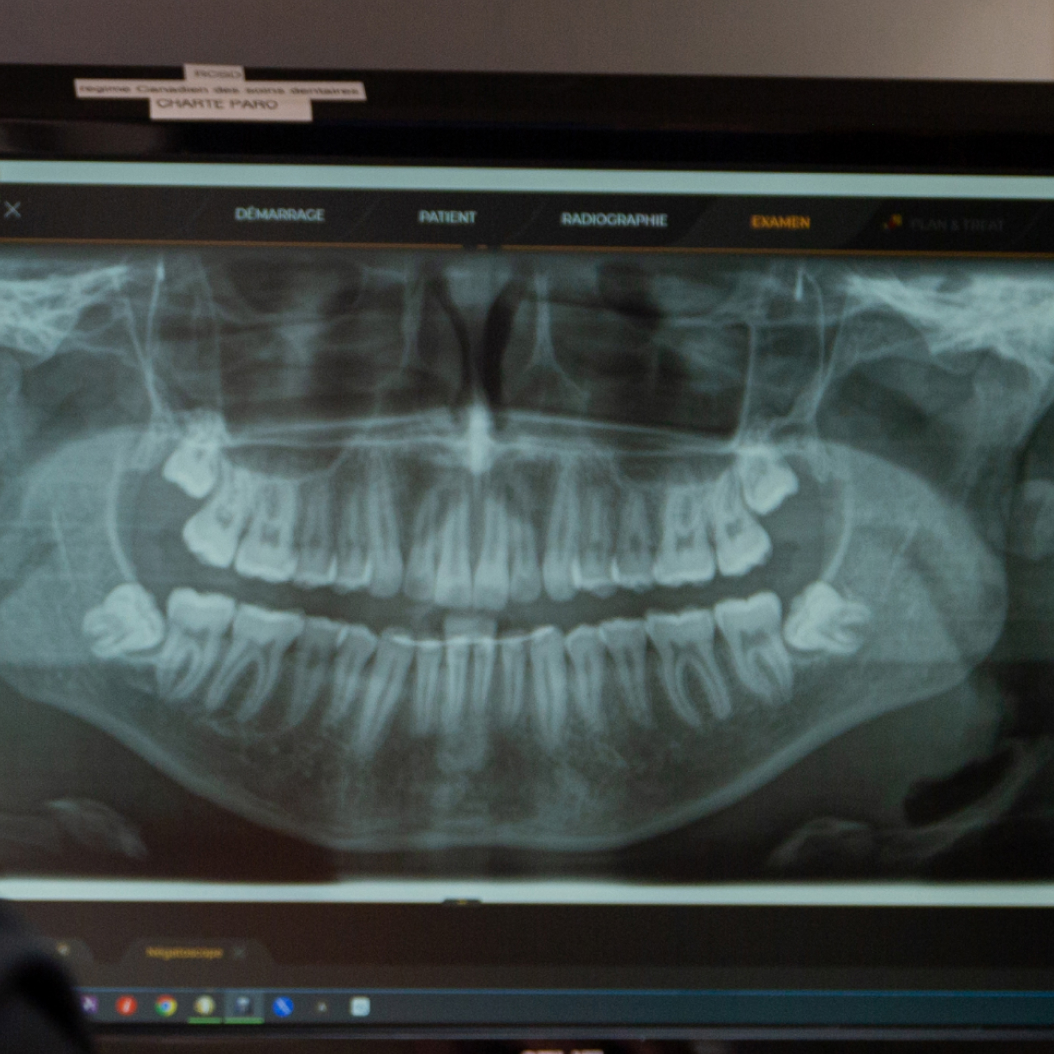

Examen bucco-dentaire complet

La base de notre pratique générale réside dans un examen dentaire complet. Le Dr Lévesque se fait un devoir de dresser un portrait fidèle de votre condition buccale. Cet examen est primordial à tout âge indépendamment de votre acuité en matière d’hygiène buccale.

L’examen bucco-dentaire complet consiste en une inspection visuelle en plusieurs points, notamment :

• les dents;

• la langue;

• les gencives;

• le palais;

• l’intérieur des joues;

• les tissus mous.

Le dentiste peut également examiner la région du cou (glandes et ganglions) et demander des radiographies.